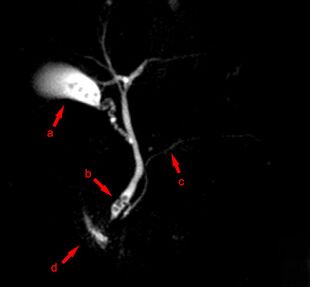

MRCP image showing stones in the distal common bile duct: (a) Gallbladder with stones, (b) Stones in bile duct, (c) Pancreatic duct, (d) Duodenum. |

Magnetic resonance cholangiopancreatography (MRCP) is a medical imaging technique. It uses magnetic resonance imaging to visualize the biliary and pancreatic ducts non-invasively. This procedure can be used to determine whether gallstones are lodged in any of the ducts surrounding the gallbladder.